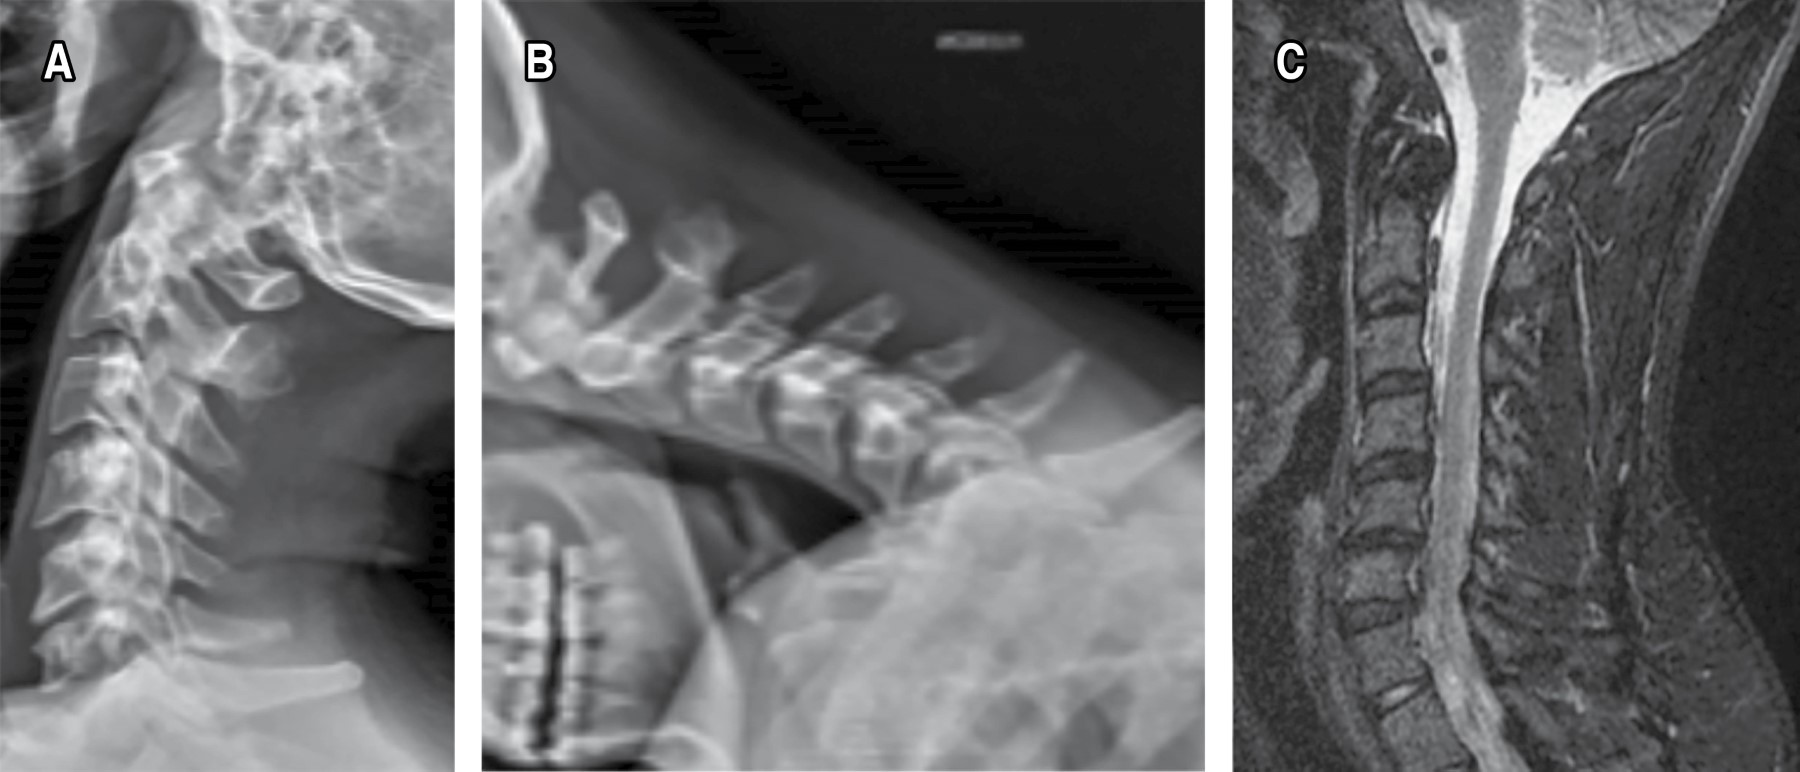

Introduction: cervical disc arthroplasty as a surgical treatment of spondylosis is a technique that has gained popularity in recent years with the advantage of maintaining movement and reducing the development of adjacent segment disease. Despite this, it is not free of complications, one of the least frequent being implant dislocation, with very few official reports in the global literature. A case report of a Baguera C type prosthesis is presented, a bibliographic review is carried out covering the different prosthetic devices that have an official report in the literature, frequencies, associated factors and treatment used are analyzed. Clinical case: 30-year-old male undergoing surgery for long-standing neck pain and myelopathy secondary to C5-C6 disc herniation and C6-C7 spondylosis. Hybrid cervical arthroplasty was performed with placement of a Baguera C disc prosthesis at C5-C6 and a CeSPACE interbody spacer at C6-C7. 13 months later he returned to the clinic with pain and refractory symptoms, X-rays were taken showing posterior dislocation of the implant. Revision surgery was performed, removing the implant, placing an interbody spacer plus bone graft, and placing an anterior locked plate with complete remission of symptoms. Conclusions: prosthetic dislocation is rare, the literature reports few cases, this being the first related to the Baguera C prosthesis, surgical treatment is imperative. The female sex and the C5-C6 level are the most affected, the previous variant is the most common. Careful placement and proper selection of the implant size are the most important factors to take into account and reduce the chances of failure. When it occurs, arthrodesis is usually the most used option with favorable results.

Figure 1